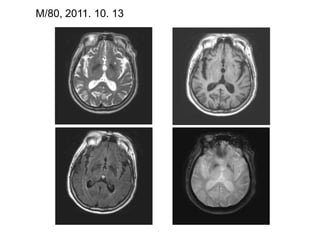

M/80, 2011. 10. 13

1. Perivascular spaces (etatcrible) MRI definition (ref. 1): the punctiform dilatations of the perivascular spaces often seen by brain MRI in the white  matter and in the basal ganglia

1. Perivascular spaces(etatcrible) MRI definition (ref. 1): the punctiform dilatations of the perivascular spaces often seen by brain MRI in the white matter and in the basal ganglia